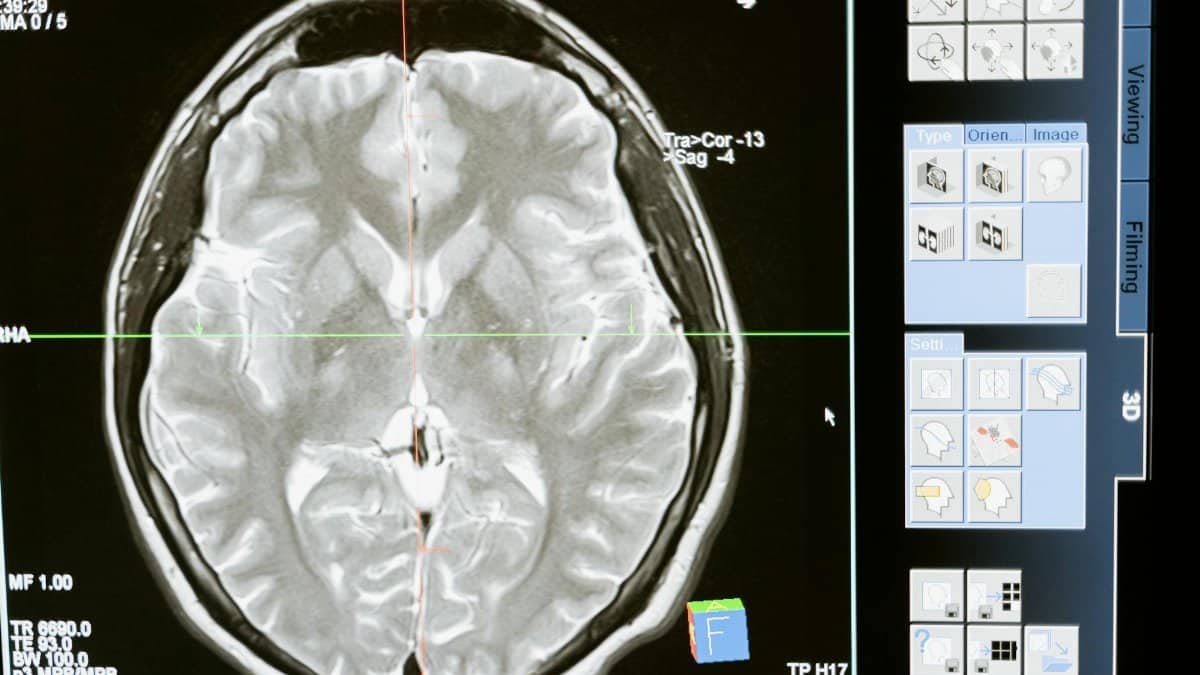

Deep in the brain lies the basal ganglia, a cluster of structures acting as the autopilot for habits. Researchers have long observed how it takes over repetitive actions, freeing the prefrontal cortex for higher thinking. Consider a smoker reaching for a cigarette without conscious thought. The NINDS explains this shift clearly in its overview of brain functions: habits form when neural circuits strengthen through repetition, turning effort into instinct.NINDS Brain Basics.

That smoker might describe it simply during a quit attempt. “One day, the pack just appeared in my hand,” he said in a casual interview snippet. No decision involved. This handover happens gradually. Early on, deliberate focus dominates. Later, cues trigger seamless execution. Experiments with rats navigating mazes confirm it: once the path becomes habitual, brain scans show basal ganglia lighting up, not the planning regions.

Charles Duhigg popularized the loop, but neuroscience backs it solidly. Cues spark the routine; rewards seal it. Functional MRI scans reveal the striatum activating in sequence. A cue—like a phone notification—prompts checking social media. The dopamine from likes rewards it.

The brain reshapes itself—neuroplasticity at work. Synapses strengthen with use, prune with neglect. Habit formation neuroscience thrives here. Meditation apps leverage it, thickening prefrontal areas over months.

A Vietnam vet rebuilt routines post-trauma. Daily journaling rewired stress responses. Scans before and after showed cortical growth. Though individual paths vary, consistency drives plasticity. Start small. A two-minute meditation snowballs.